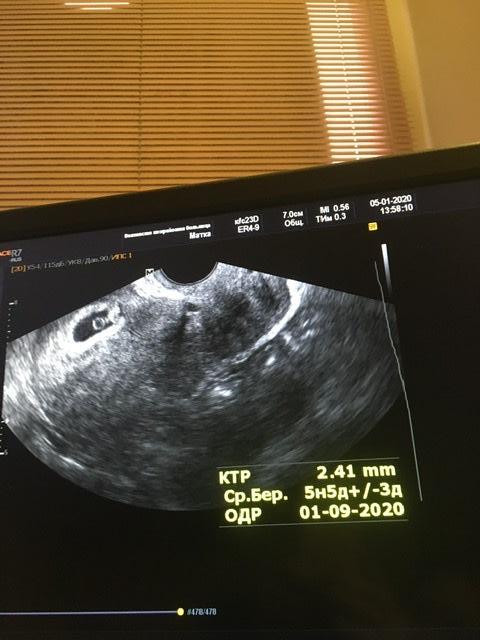

Сохранение ЭКО-беременностиДобрый вечер. Вопрос скорее к уже более беременным эко-мамам)))

29дпп. Выделения. Поехала в больницу. Ставят капельницы с транексамом. Поддержка вся моя.

Но вот вопрос - у кого так было- вообще сказали от чего это бывает? Местные врачи мне вообще ничего не говорят. Узи в норме(по их словам) . Но больница обычная. И что делать с эко они вообще не в курсе. Так и говорят - что то мажет. Все свое пей и лежи.